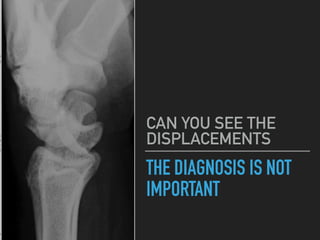

THE DIAGNOSIS IS NOT

IMPORTANT

CAN YOU SEE THE

DISPLACEMENTS

NOT SO DIFFICULT IS IT!

THIS IS A MIDCARPAL DISLOCATION

▸ BOTH THE CAPITATE AND

LUNATE ARE DISPLACED

▸ THE MOST IMPORTANT THING IS

TO SPOT THE DISPLACEMENT,

THE FINAL DIAGNOSIS IS MADE

BY AN ORTHOPAEDIC SPECIALIST

▸ BUT THEY WILL BE IMPRESSED IF

YOU PICK IT UP

THE DIAGNOSIS ISNOT IMPORTANT CAN YOU SEE THE DISPLACEMENTS

NOT SO DIFFICULTIS IT! THIS IS A MIDCARPAL DISLOCATION ▸ BOTH THE CAPITATE AND LUNATE ARE DISPLACED ▸ THE MOST IMPORTANT THING IS TO SPOT THE DISPLACEMENT, THE FINAL DIAGNOSIS IS MADE BY AN ORTHOPAEDIC SPECIALIST ▸ BUT THEY WILL BE IMPRESSED IF YOU PICK IT UP